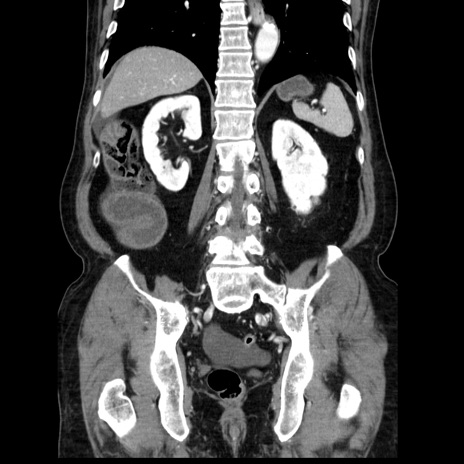

症例30(冠状断像)

【症例】80歳代男性

【主訴】臍周囲痛

【現病歴】約6時間前から臍下部痛が出現。次第に腹部膨隆・背部痛も生じてきたため来院。背部痛の場所は変化しない。

【身体所見】意識清明、BT 36.3℃、BP  131/87mmHg、P 87bpm、SpO2 100%(RA)、臍周囲自発痛・圧痛あり、反跳痛なし、自発痛部位に一致して板状硬あり、腹部膨隆、腸雑音減弱、CVA tenderness両側陰性。

【データ】WBC 19600、CRP 0.33